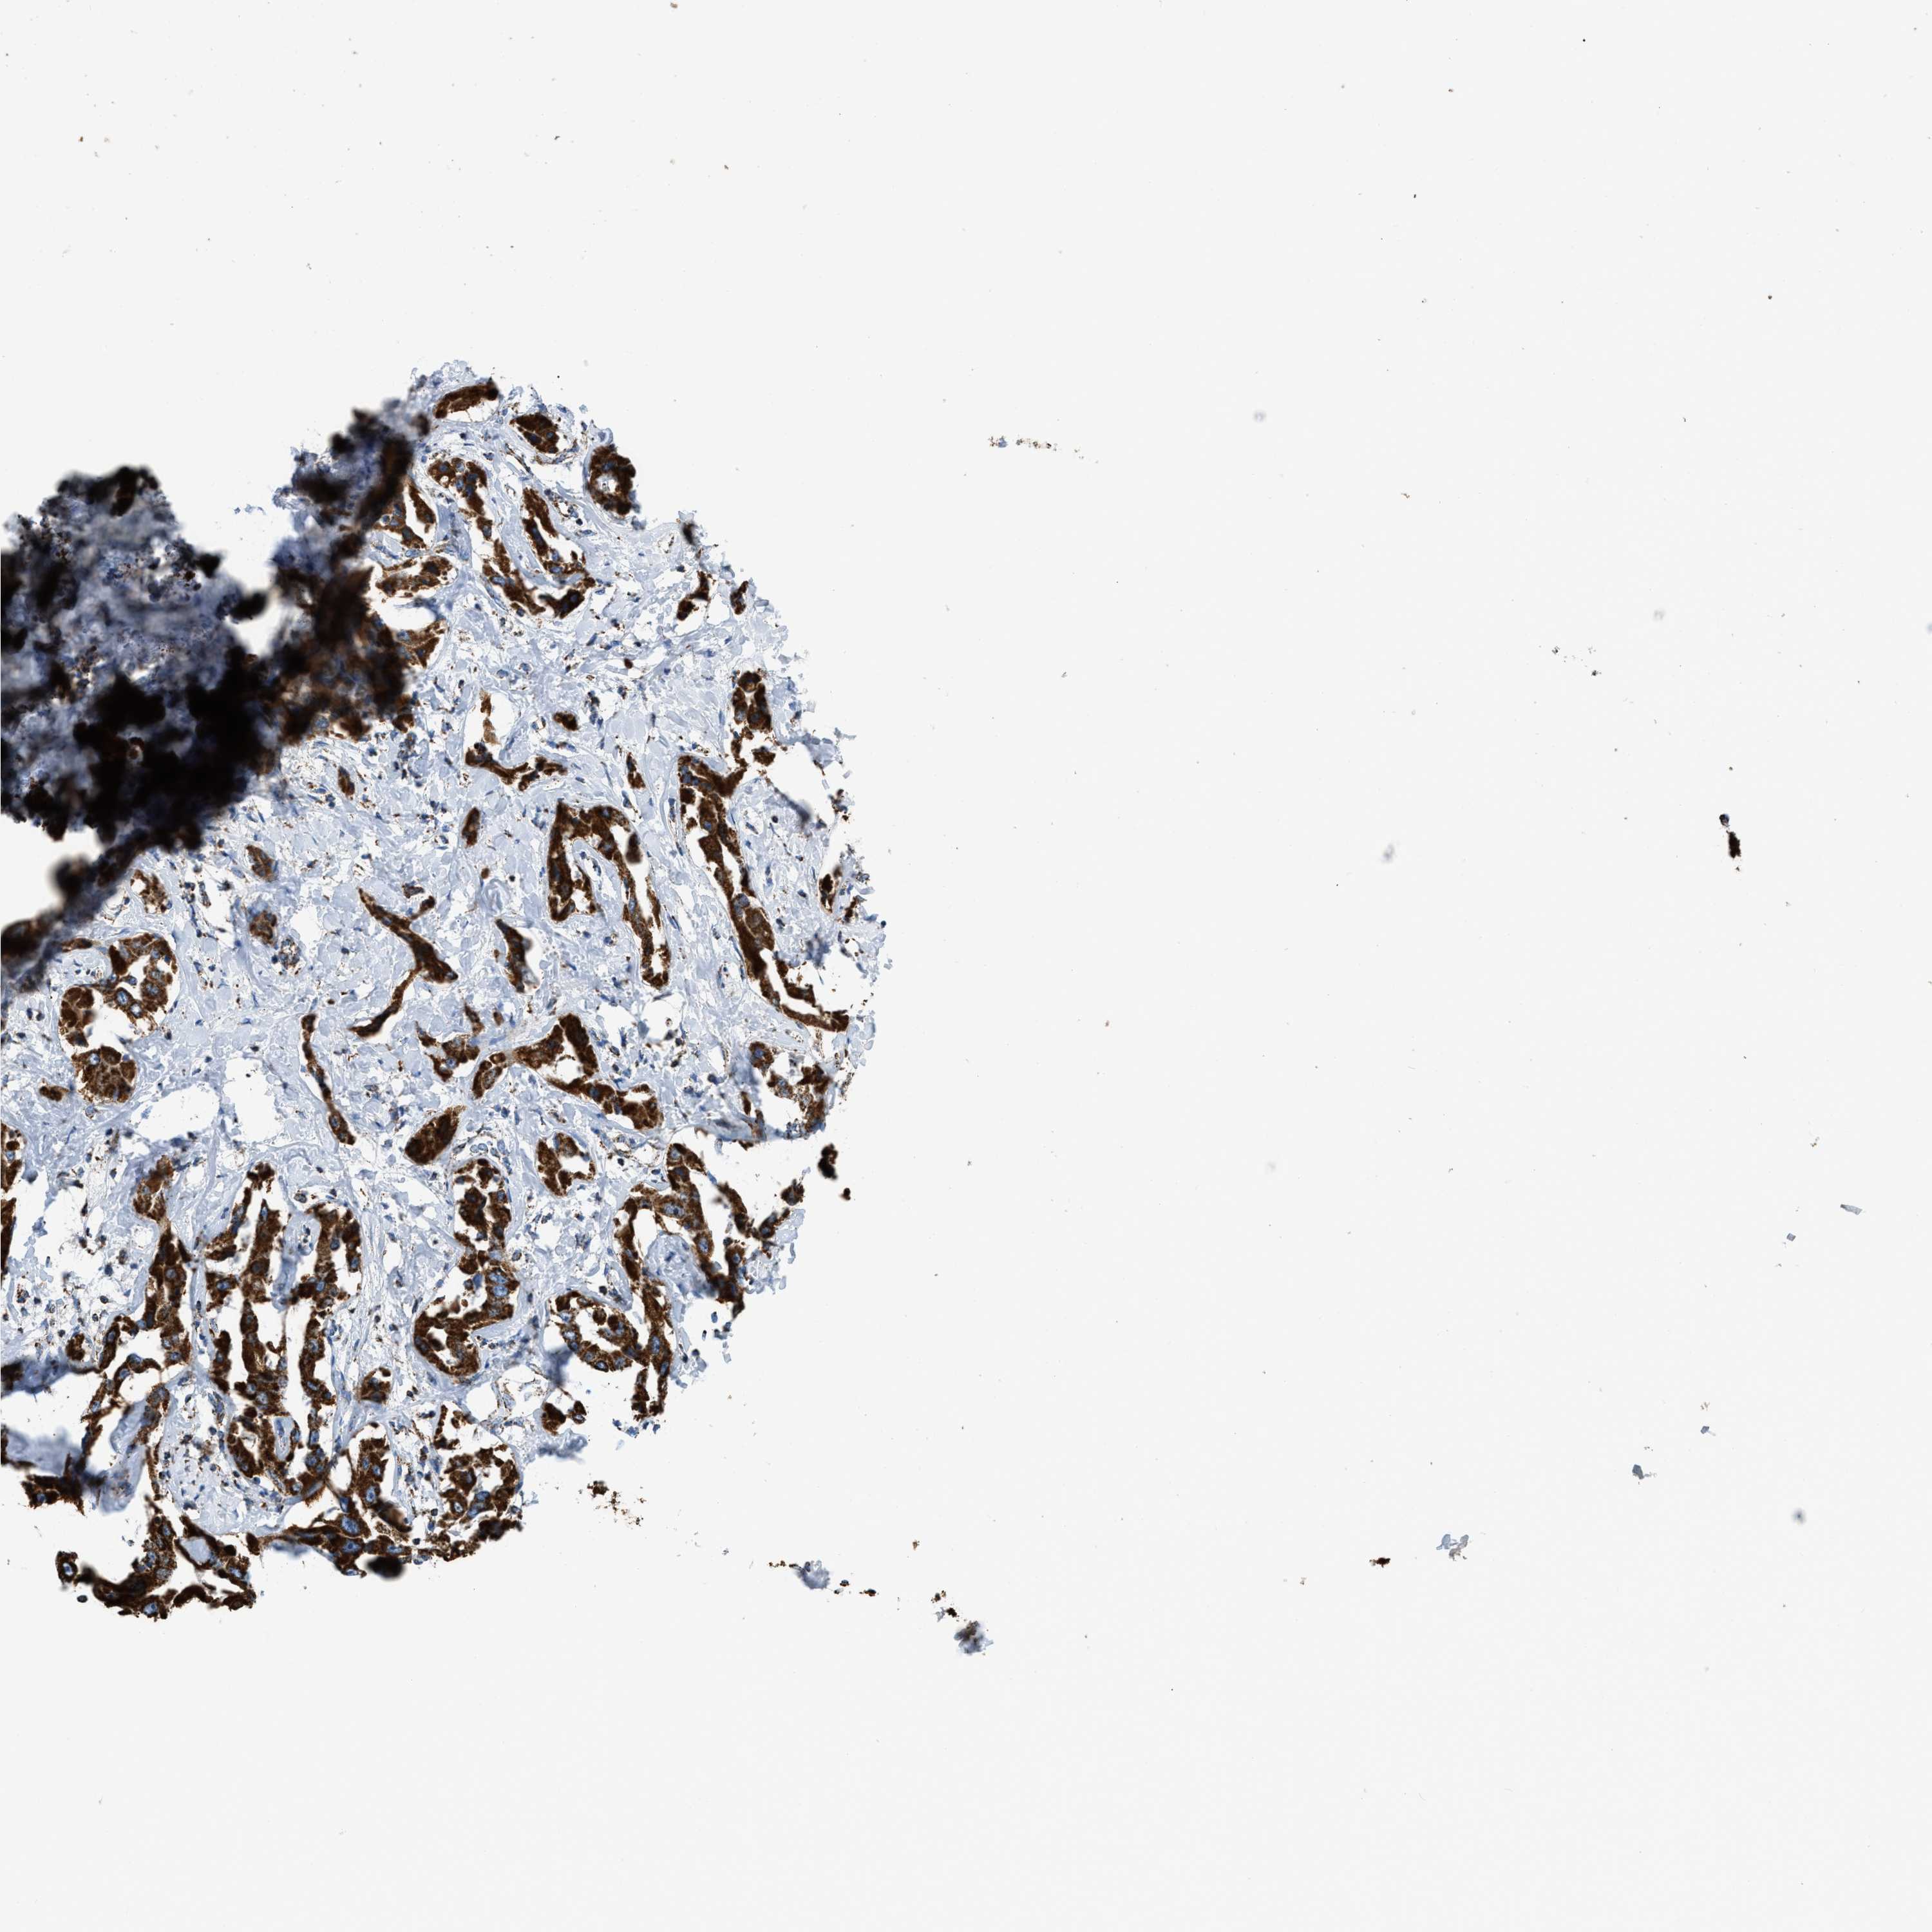

LIVER CANCER - Protein expressioni

A mouse-over function shows sample information and annotation data. Click on an image to view it in a full screen mode. Samples can be filtered based on level of antibody staining by selecting one or several of the following categories: high, medium, low and not detected. The assay and annotation is described here.

Note that samples used for immunohistochemistry by the Human Protein Atlas do not correspond to samples in the TCGA dataset.

Antibody stainingi

Antibody staining in the annotated cell types in the current human tissue is reported as not detected, low, medium, or high, based on conventional immunohistochemistry profiling in selected tissues. This score is based on the combination of the staining intensity and fraction of stained cells.

Each image is clickable and will lead to virtual microscopy that enables deeper exploration of all samples and also displays staining intensity scores, fraction scores and subcellular localization as well as patient and tissue information for each sample.

Antibody HPA018910

Antibody HPA018921

Antibody HPA018923

Staining

High

Medium

Low

Not detected

Intensity

Strong

Moderate

Weak

Negative

Quantity

>75%

75%-25%

<25%

None

Location

Nuclear

Cytoplasmic/membranous

Cytoplasmic/membranous,nuclear

Cholangiocarcinoma

Carcinoma, Hepatocellular, NOS